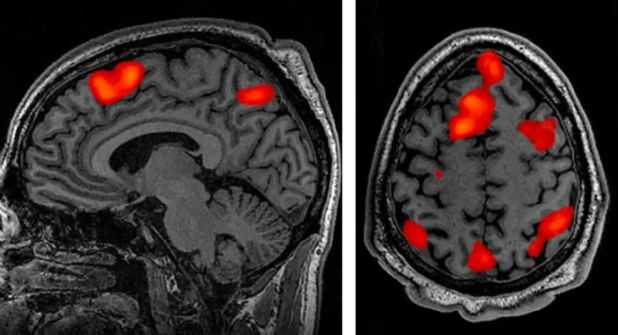

Reveló que en los 30 segundos anteriores y posteriores, las ondas cerebrales del hombre siguieron los mismos patrones que los sueños o los recuerdos.

La actividad cerebral de este tipo podría sugerir que un "recuerdo de la vida" final puede ocurrir en los últimos momentos de una persona, escribió el equipo en su estudio, publicado en Frontiers in Aging Neuroscience.

El Dr. Zemmar, ahora neurocirujano de la Universidad de Louisville, dijo que en los 30 segundos antes de que el corazón del paciente dejara de suministrar sangre al cerebro, sus ondas cerebrales siguieron los mismos patrones que cuando llevamos a cabo tareas exigentes de alto nivel cognitivo, como concentrarse, soñar o recordando recuerdos.

Continuó 30 segundos después de que el corazón del paciente dejó de latir, el punto en el que generalmente se declara muerto a un paciente.